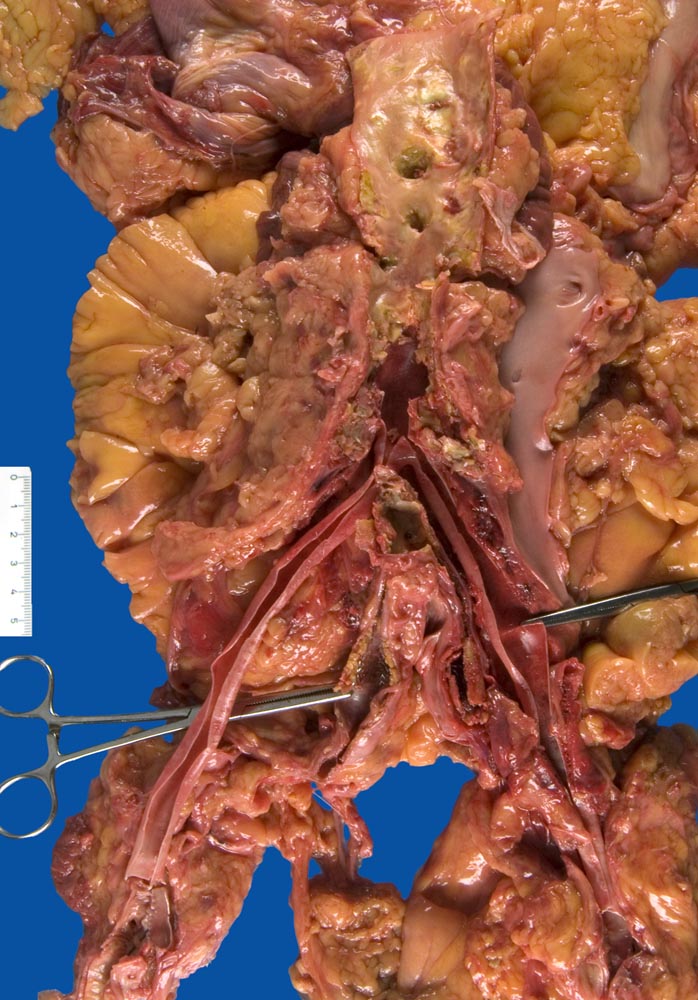

PathoPic – image database / PathoPic ID 9885 - Aortobifemoraler Bypass und Stent in der Arteria iliaca communis

Aortobifemoraler Bypass und Stent in der Arteria iliaca communis

vaskulär / Durchblutungsstörung

Aorta abdominalis

Kardiovaskuläres System

Zusatzbefund

Linksherzversagen bei akutem transmuralem Myokardinfarkt. Duodenalulzera.

St.n. aortobifemoralem Bypass bei PAVK Grad III vor zwei Wochen. St.n. Einlage eines Stent in die A. iliaca communis links vor 7 Jahren.

Respiratorische Insuffizienz und Kreislaufversagen bei

V.a. hämorrhagischen Schock mit Linksherzdekompensation. Blutungsquelle?